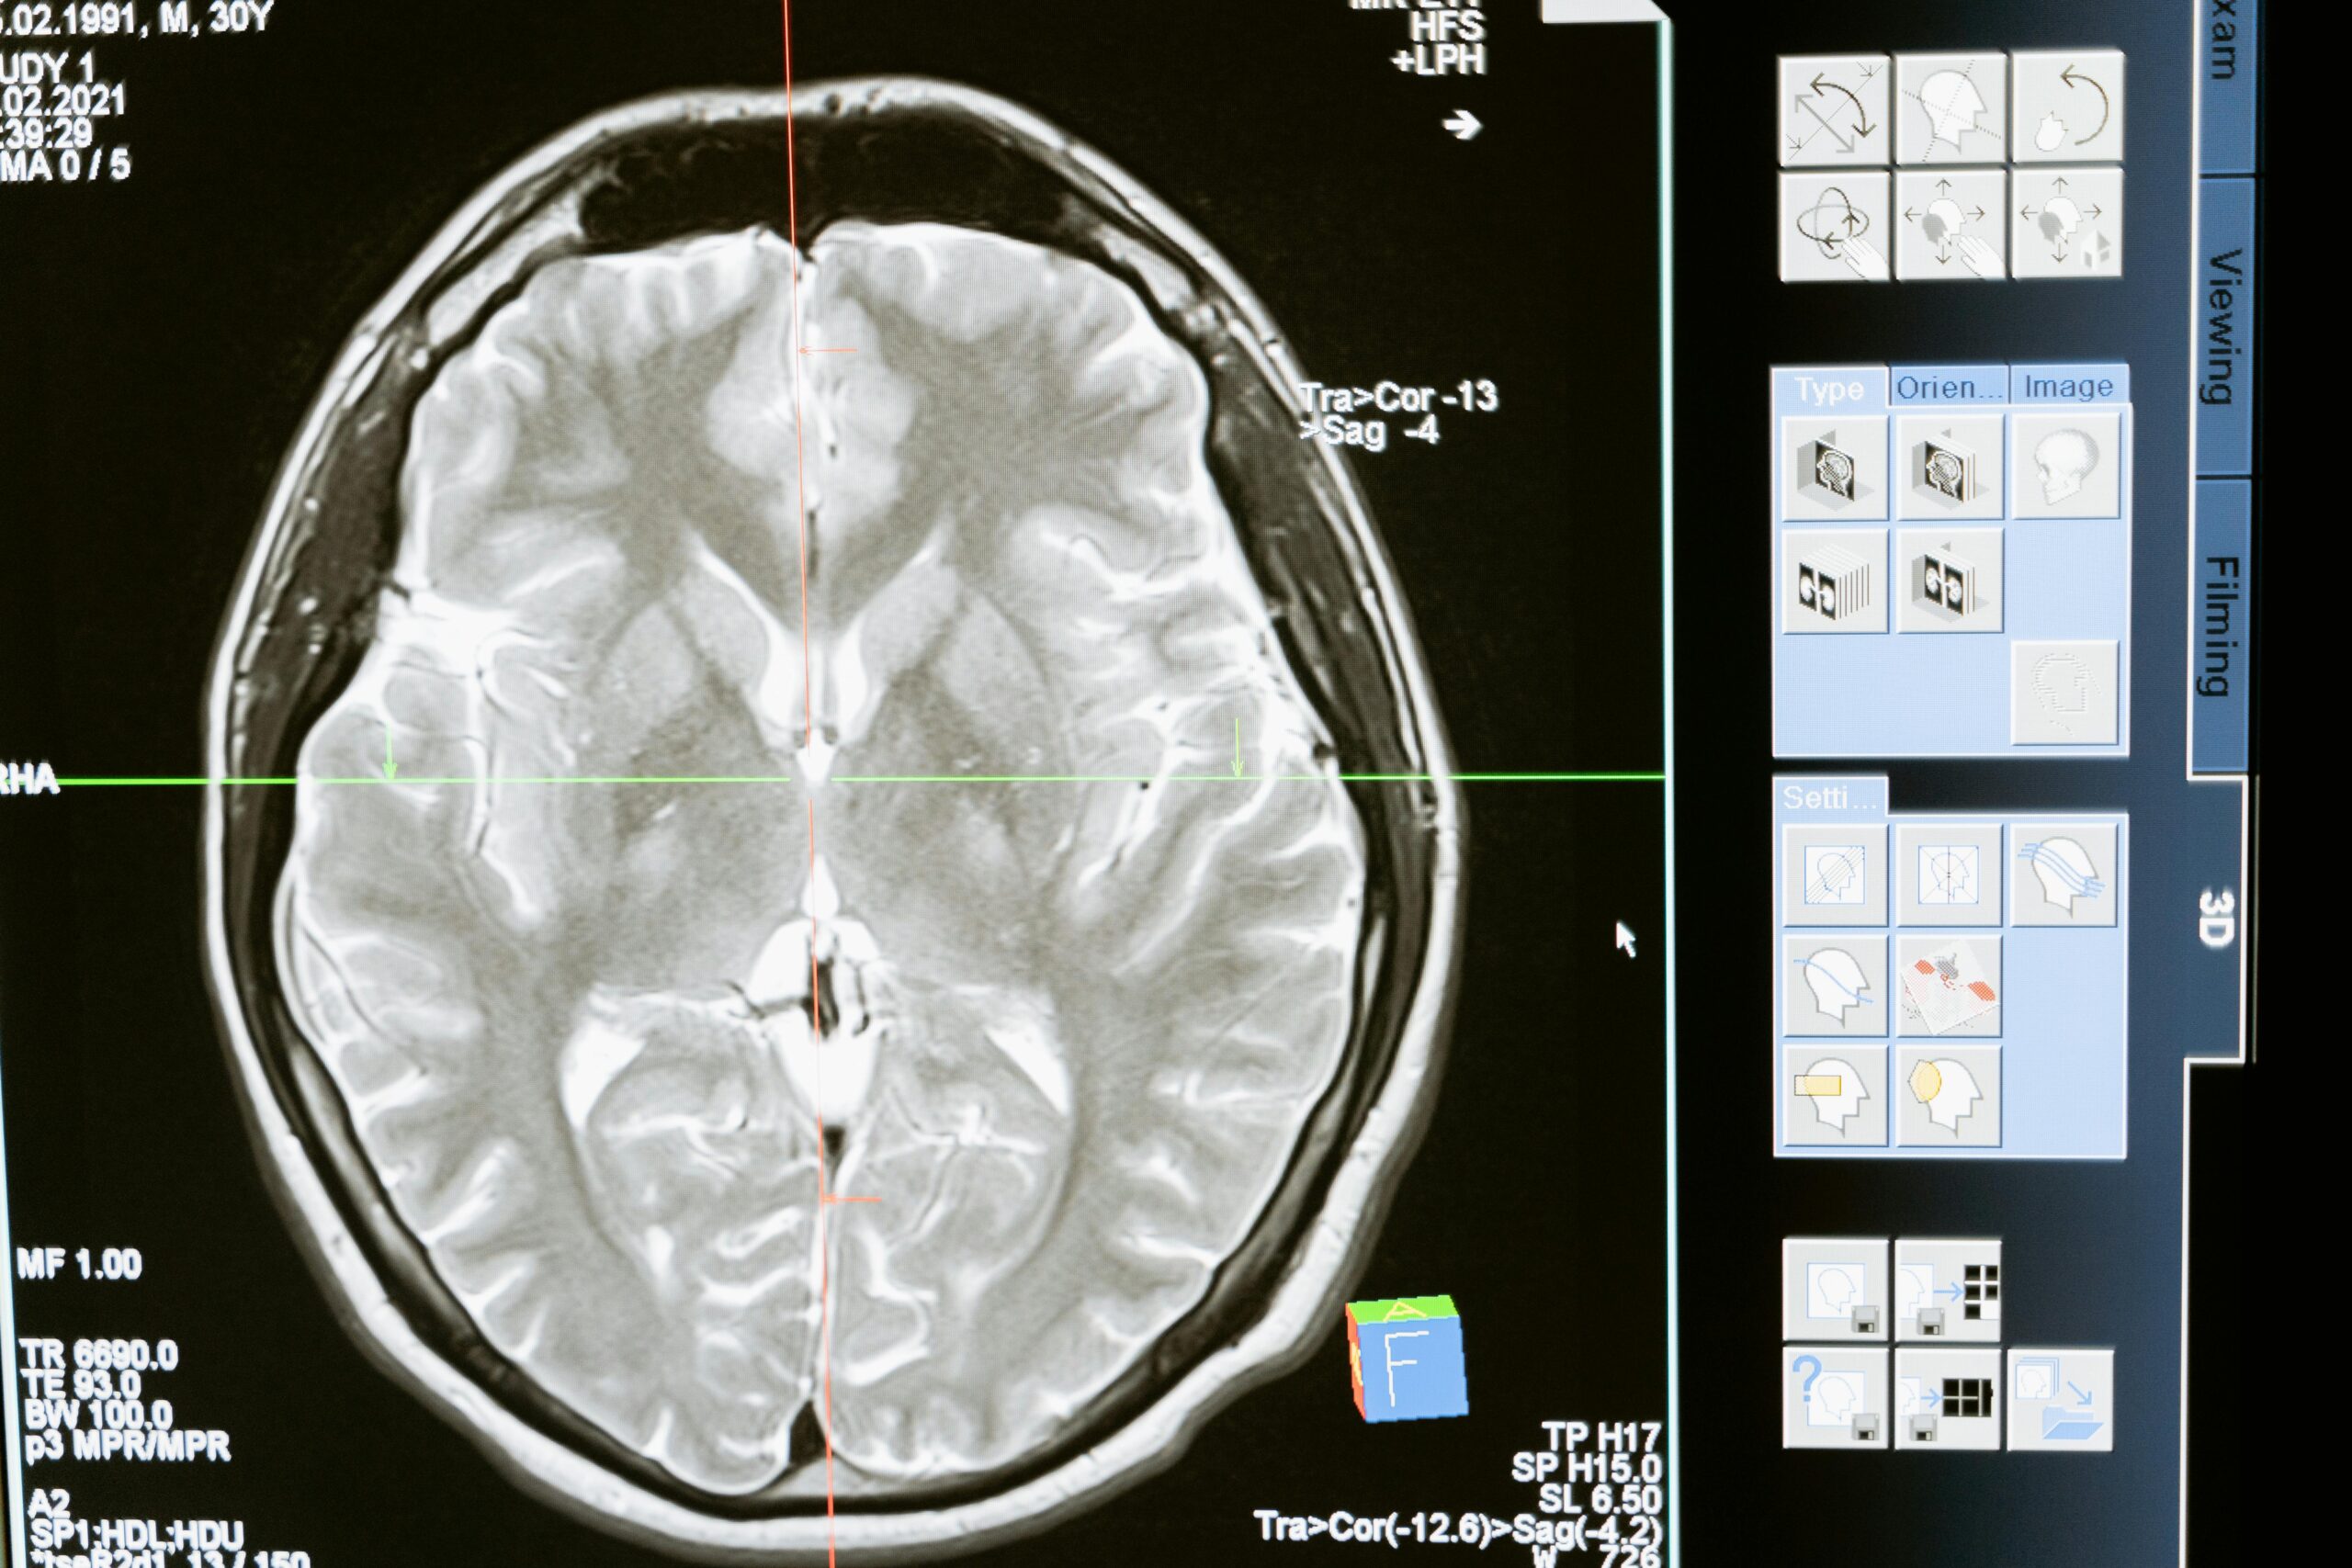

Zatímco ještě před zhruba 30 lety byla koktavost považována za problém čistě psychologického původu, dnes ji vědci připisují celé řadě faktorů, které mohou přispívat k jejímu rozvoji. Bylo například identifikováno několik genů, které zvyšují riziko koktání, a mozky lidí s poruchami plynulosti řeči se v nervových spojeních a mozkové aktivitě anatomicky liší od lidí, kteří mluví plynule.

Dr. Christian Kell, neurolog a ředitel Cooperative Brain Imaging Center na Univerzitě Johannese Wolfganga Goetha ve Frankfurtu, vysvětluje: „Levá hemisféra mozku dokáže zpracovávat signály, které se objevují v rychlém sledu. U lidí, kteří koktají, však sluchová kůra v levé hemisféře méně spolupracuje s motorickou kůrou, která ovládá svaly zapojené do řeči. Mozek v důsledku toho může tyto úkoly delegovat na pravou hemisféru, která si s rychlými signály typickými pro řeč hůře poradí.“ Výsledkem je, že ačkoli postižení lidé přesně vědí, co chtějí říct, zaseknou se na určitých slovech.

Po rozsáhlé přípravě a na opakovanou žádost pacienta týmy z Frankfurtu a Münsteru implantovaly muži, který koktá, do levého talamu vlasově tenký drátek. Talamus je centrální přepojovací stanice hluboko v mozku. Prostřednictvím drátu byla tato oblast stimulována slabými elektrickými impulzy. Standardizované testy pak měřily, jak se pacientovo koktání změnilo.